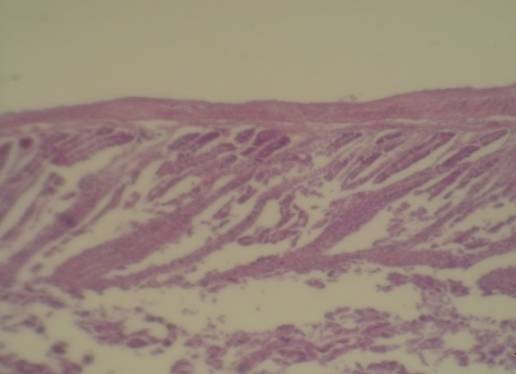

Железистый эпителий гиперхромный, полиморфный. Мышечный слой стенок истончен,

склерозирован (рисунок 2).

Рисунок 2. Железистый эпителий гиперхромный, полиморфный. Мышечный слой стенок истончен, склерозирован. Увеличение: объектив 10., окуляр 40. Окраска: гематоксилин с эозином.